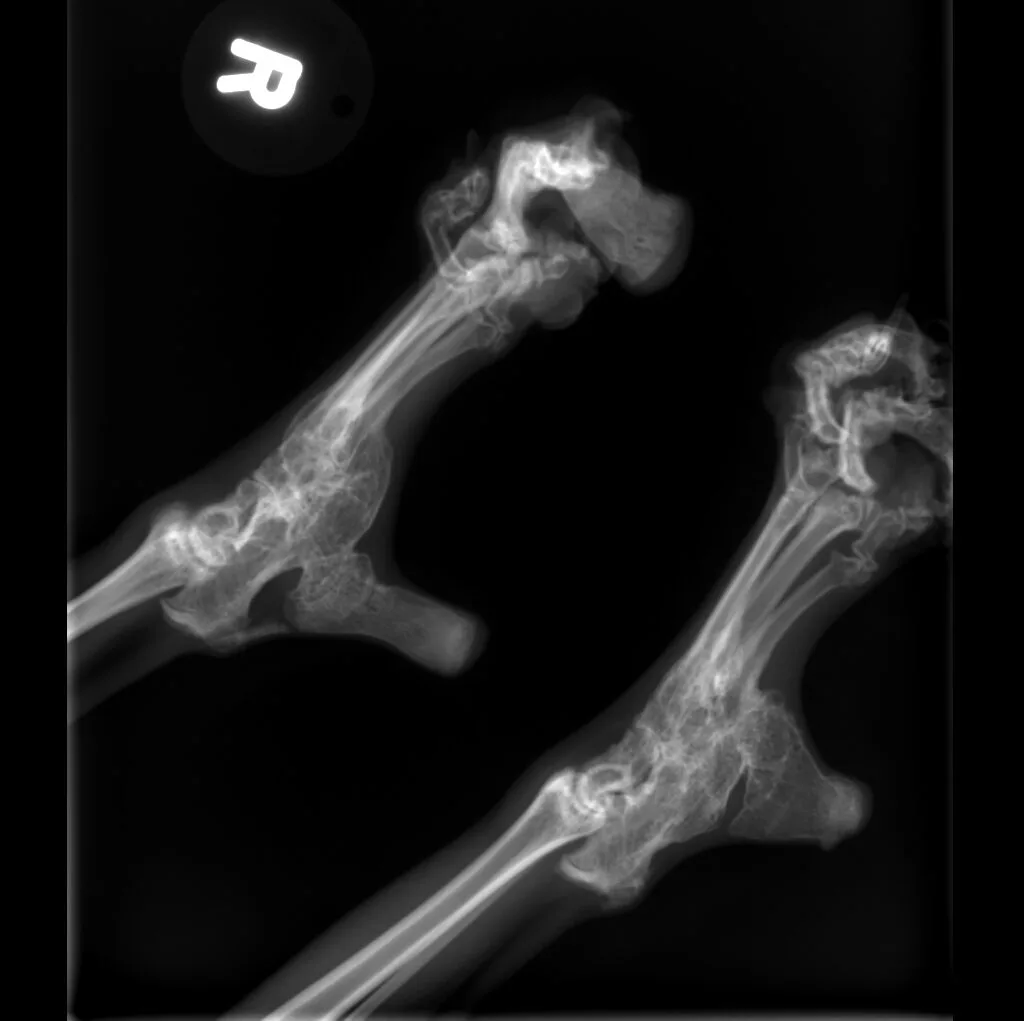

🔹 Lameness & Joint Issues – Identifying fractures, arthritis, and mobility concerns